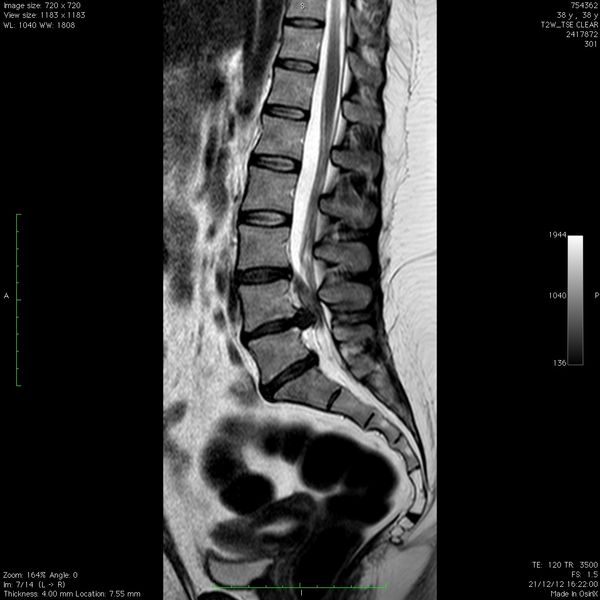

En Marchante Gago, hemos desarrollado un programa exclusivo para el tratamiento de protusiones y hernias discales en columna vertebral, basado en nuestra amplia experiencia.

Este programa está diseñado para ofrecer una solución eficaz, personalizada y no invasiva, adaptada a las necesidades de cada persona.

Personas con diagnóstico confirmado de protusión o hernia discal.